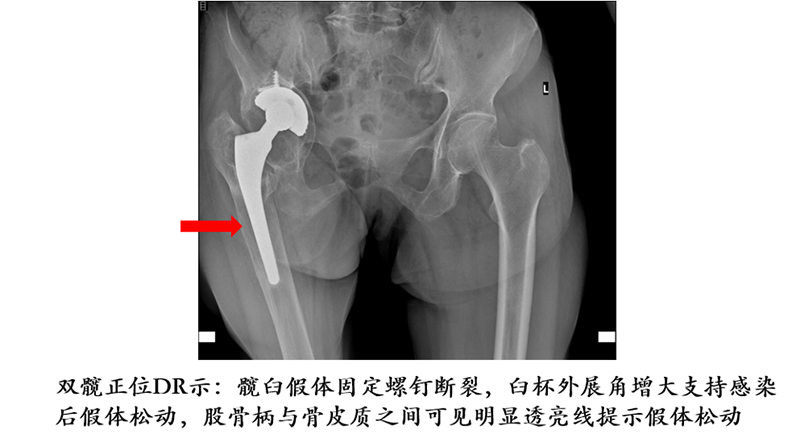

2、感染以后引起松动,这也是一个比较常见的松动原因;

1.进行手术治疗前,需要进行鉴别诊断,明确松动的部位,如髋臼、股骨柄、内衬。

2.查找到病因,如无菌性松动或者感染造成的松动,通过一系列临床检查来鉴别诊断。如果是感染性松动,需要进行彻底翻修,二期置换,或在有条件的情况下进行一期翻修置换。如果为单纯某一部位无菌性松动,可以根据情况选择合适假体部件进行更换,要根据不同病人,不同病情来选择合适的治疗方案。出现假体松动一定要重视,积极进行诊治,不要让病情日益发展,耽误合适治疗时机。